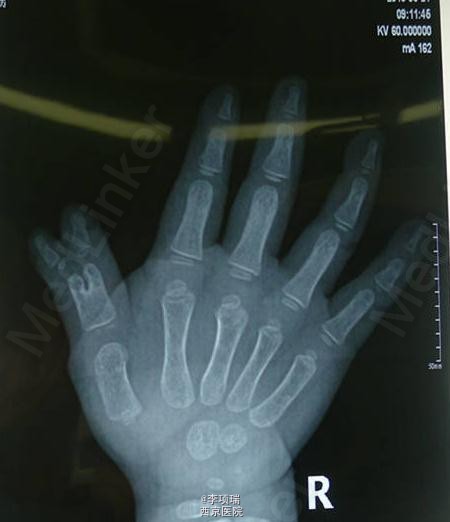

3型多指传统BC融合术

患儿,男,2岁4月,右拇3型复拇,家长选择融合术。